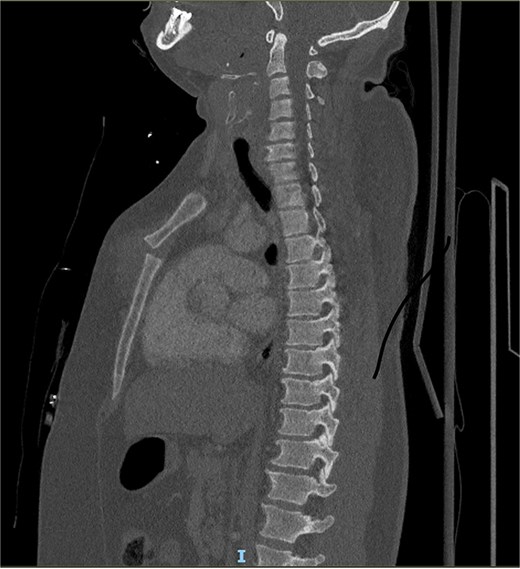

A 39-year-old male was admitted to our department after a severe crush with a forklift truck on his ribcage/thorax while at work. On arrival, he was conscious with stable vital signs (blood pressure 151/73, heart rate: 78 bpm, and saturation of 100% under 5 l) but complained of heavy right arm and chest pain. The clinical examination revealed an obese patient with a calculated BMI of 41 with a hematoma over the sternum and increased tenderness to palpation with no apparent instability. Deformity of the right arm with nerve damage in the radial territory was also noted. He had no previous medical history. The 3D computed tomography (CT) showed a type I MSD with osteochon dral dehiscence at the level of rib two bilaterally on the sternal side and ribs 4–6 left on the costal side with non-displaced bowing rib fracture of ribs seven and eight anteriorly on the left. An associated small pneumothorax, restricted pneumomediastinum, and the presence of a lung contusion posteriorly on both sides. No laceration, no pleural fluid (Fig. 1). The radiography of the arm showed a transverse, multi-fragmentary mid-diaphysis humeral fracture with bayonet position and significant angulation. The patient was first admitted to the intensive care unit (ICU) for surveillance; pain management was provided with a patient-controlled intravenous analgesia (PCIA) opioid pump, and 3-liter oxygen therapy was administered. The indication for reduction was primarily the severe displacement of the manubrio-sternal junction associated with the chondro-costal dehiscence. The overall stability of the fracture was challenging to assess due to the severe obesity, making a closed reduction even more difficult. Regarding the imagery, we assume that the thoracic cage’s overall stability would be insufficient. Secondly, the patient presented with persistent pain with the need for intravenous opioids. Finally, the patient had to undergo another operation for which the same general anesthesia could stabilize both fractures. After four days of scheduling, the patient underwent a chest wall reconstruction under general anesthesia associated with a patient-controlled epidural analgesia (PCEA). The patient was installed in a supine position with arms abducted. A 15 cm bi-submammary incision up to the sternal fork was realized. Dissection until manubriosternal dislocation was retrieved, reduction was obtained with two 8-hole locking compression plates and secured with 16- and 18-mm screws. Since the chondro-sternal fracture was not eligible between the cartilage and bone for direct osteosynthesis, we performed a fixation at the level of ribs 4–5 bilaterally using titanium rib clip plates stabilized between them by a titanium connecting bar. An open reduction with internal fixation treated the humeral fracture with 4,5 mm 10-hole plates. The patient was extubated directly after the procedure and received postoperative physical and respiratory therapy. He was discharged on postoperative day 4. After two months, the patient still presents limited mobilization on his right hand but has evolved favorably on the thoracic sides with no signs of sternal instability. His radiography showed a correct alignment of the manubriosternal joint (Fig. 2).